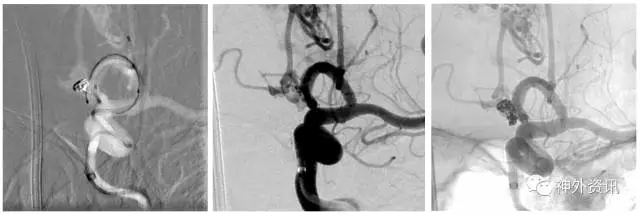

(头颅CT:蛛网膜下腔出血,右侧额叶混杂高密度占位伴局部钙化)

(脑动脉CTA:前交通动脉瘤+右侧额叶AVM)

(右侧额叶AVM:双侧大脑前动脉+右侧大脑中动脉供血,静脉引流入矢状窦)

(左侧颈内动脉优势供血前交通微小动脉瘤2枚)

(治疗计划:支架辅助弹簧圈栓塞2枚前交通动脉瘤)

(Envoa DA导引导管—左侧颈内动脉海绵窦段)

(瘤1:单纯弹簧圈栓塞致密,动脉瘤不显影)

(瘤2:支架辅助弹簧圈栓塞致密,动脉瘤不显影)

(术后3D双容积重建和Dyna CTA)